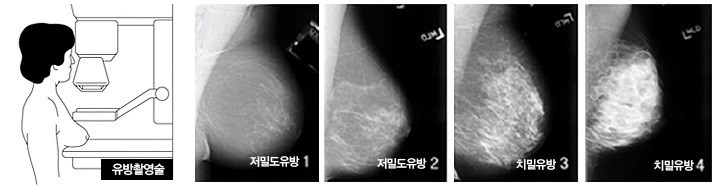

치밀 유방은 유방 조직이 꽉 차서 지방 조직보다 더 많은 비율을 차지하는 상태를 말합니다. 유방의 표면이 더 단단하고 결절 혹은 덩어리처럼 느껴질 수 있습니다. 유방 조직의 밀도가 높은 여성들에게서 더 자주 나타납니다.

▪️ 치밀 유방 특징

- 유방 조직이 흰색 영역으로 넓게 나타납니다.

- 지방 조직이 적습니다.

- 유방 촬영 시 영상이 불분명할 수 있습니다.